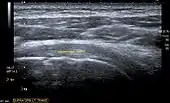

![]() Transversal ultra sonography of the supraspinatus tendon |